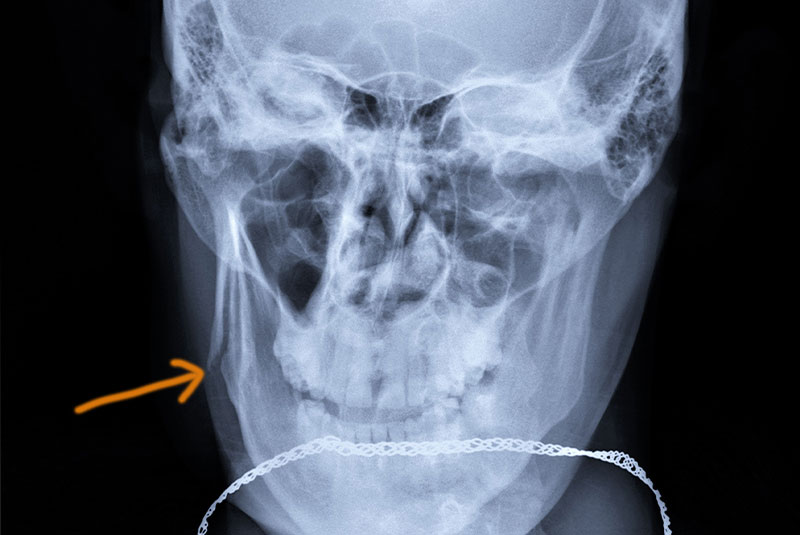

Orbital Fractures

Any of the bones in the orbital area can be broken, including the eye socket’s bony outer edges, the orbital floor, and the inner wall or floor of the socket. Surgery at Morristown Oral Surgery & Implantology Associates for more serious fractures may be needed to repair tissue prolapse and/or repair the broken bone.

Nasal Fractures

Nasal fractures frequently occur as a result of facial trauma caused by accidents, sports-related incidents, falls, and physical altercations. Closed reduction techniques gently move the bones back in place, while complex fractures may require open reduction with surgical incisions and sutures.